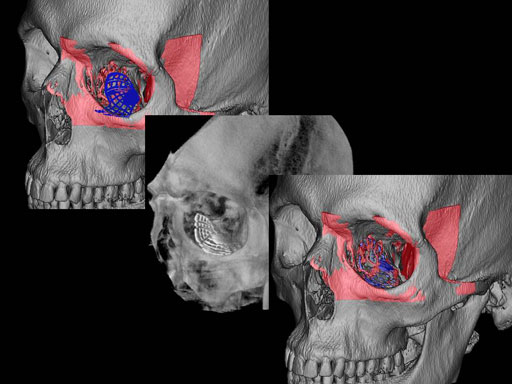

Unlike the existing two-dimensional mesh implants, the geometry of the new preformed plates will be adequate to match the individual anatomic situation of the patient in almost any case. However, the mesh parts can be individually adjusted if necessary. In these cases the solid part in the central posterior area needs to remain untouched. Areas of the orbit that do not require a bridging can be spared out by trimming the implant along the designated cutting lines in the height of the medial wall and/or length of the orbital floor area. The lateral anterior part of the plate is intentionally pre-bent higher than the orbital rim anatomy to allow free plate movement during plate positioning.

The Preformed Orbital Plates are indicated for trauma repair and reconstruction of fractures of the orbital floor, medial orbital wall or combined fractures of floor and medial wall. It should be noted that in three-wall fractures where the lateral wall is also involved, a second orbital implant, ( i. e. the mesh plate) must be used in addition to the pre-formed orbital plate.

Implant placement according to the orbital landmarks

1 Orbital rim, 2 Inferior orbital fissure, 3 Posterior orbital ledge, 4 Transition between the medial wall and orbital floor, 5 Optic canal, 6 Lacrimal fossa

30 year old male patient with fracture of left orbital floor and medial wall.

Provided by Dr Dr Marc C Metzger, Freiburg, Germany.